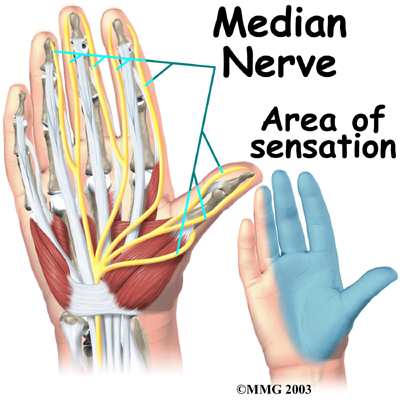

The travels through a tunnel within the wrist called the carpal tunnel. The median nerve gives sensation to the palm sides of the thumb, index finger, long finger, and half of the ring finger. It also sends a nerve branch to control the thenar muscles of the thumb. The thenar muscles help move the thumb and let you touch the pad of the thumb to the tips each of each finger on the same hand, a motion called opposition.